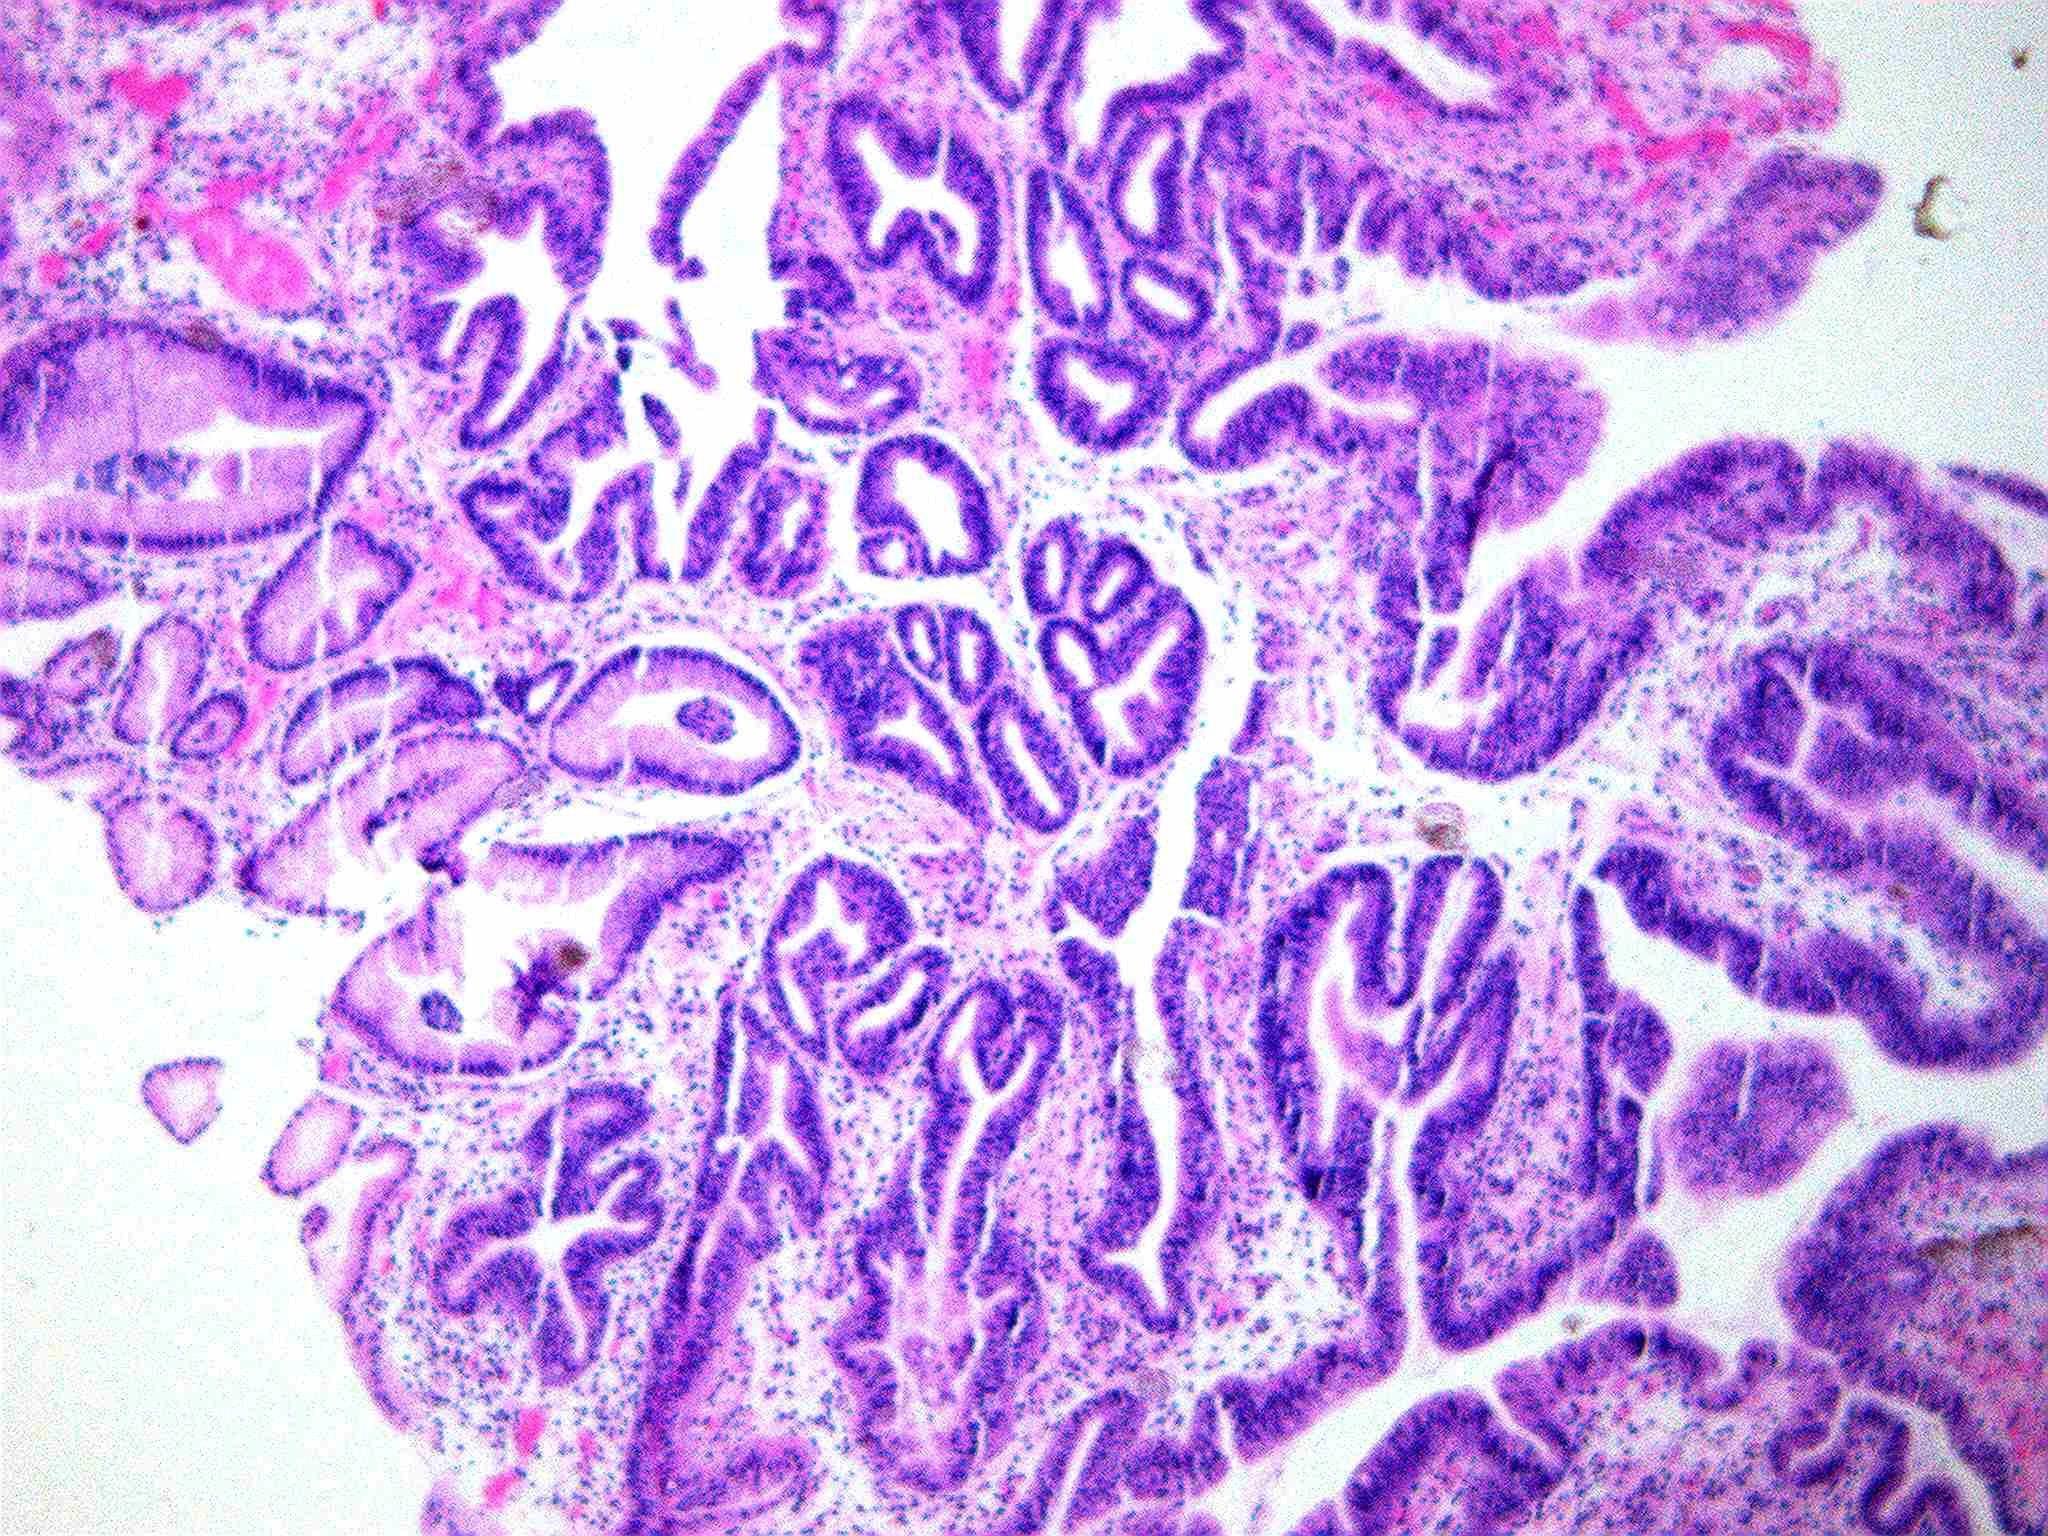

哇哦,树莓哎。小凹上皮肿瘤伴高级别上皮内瘤变,日常工作中并不常见,可惜了,只有一张白光图片~

哇哦,树莓哎。小凹上皮肿瘤伴高级别上皮内瘤变,日常工作中并不常见,可惜...